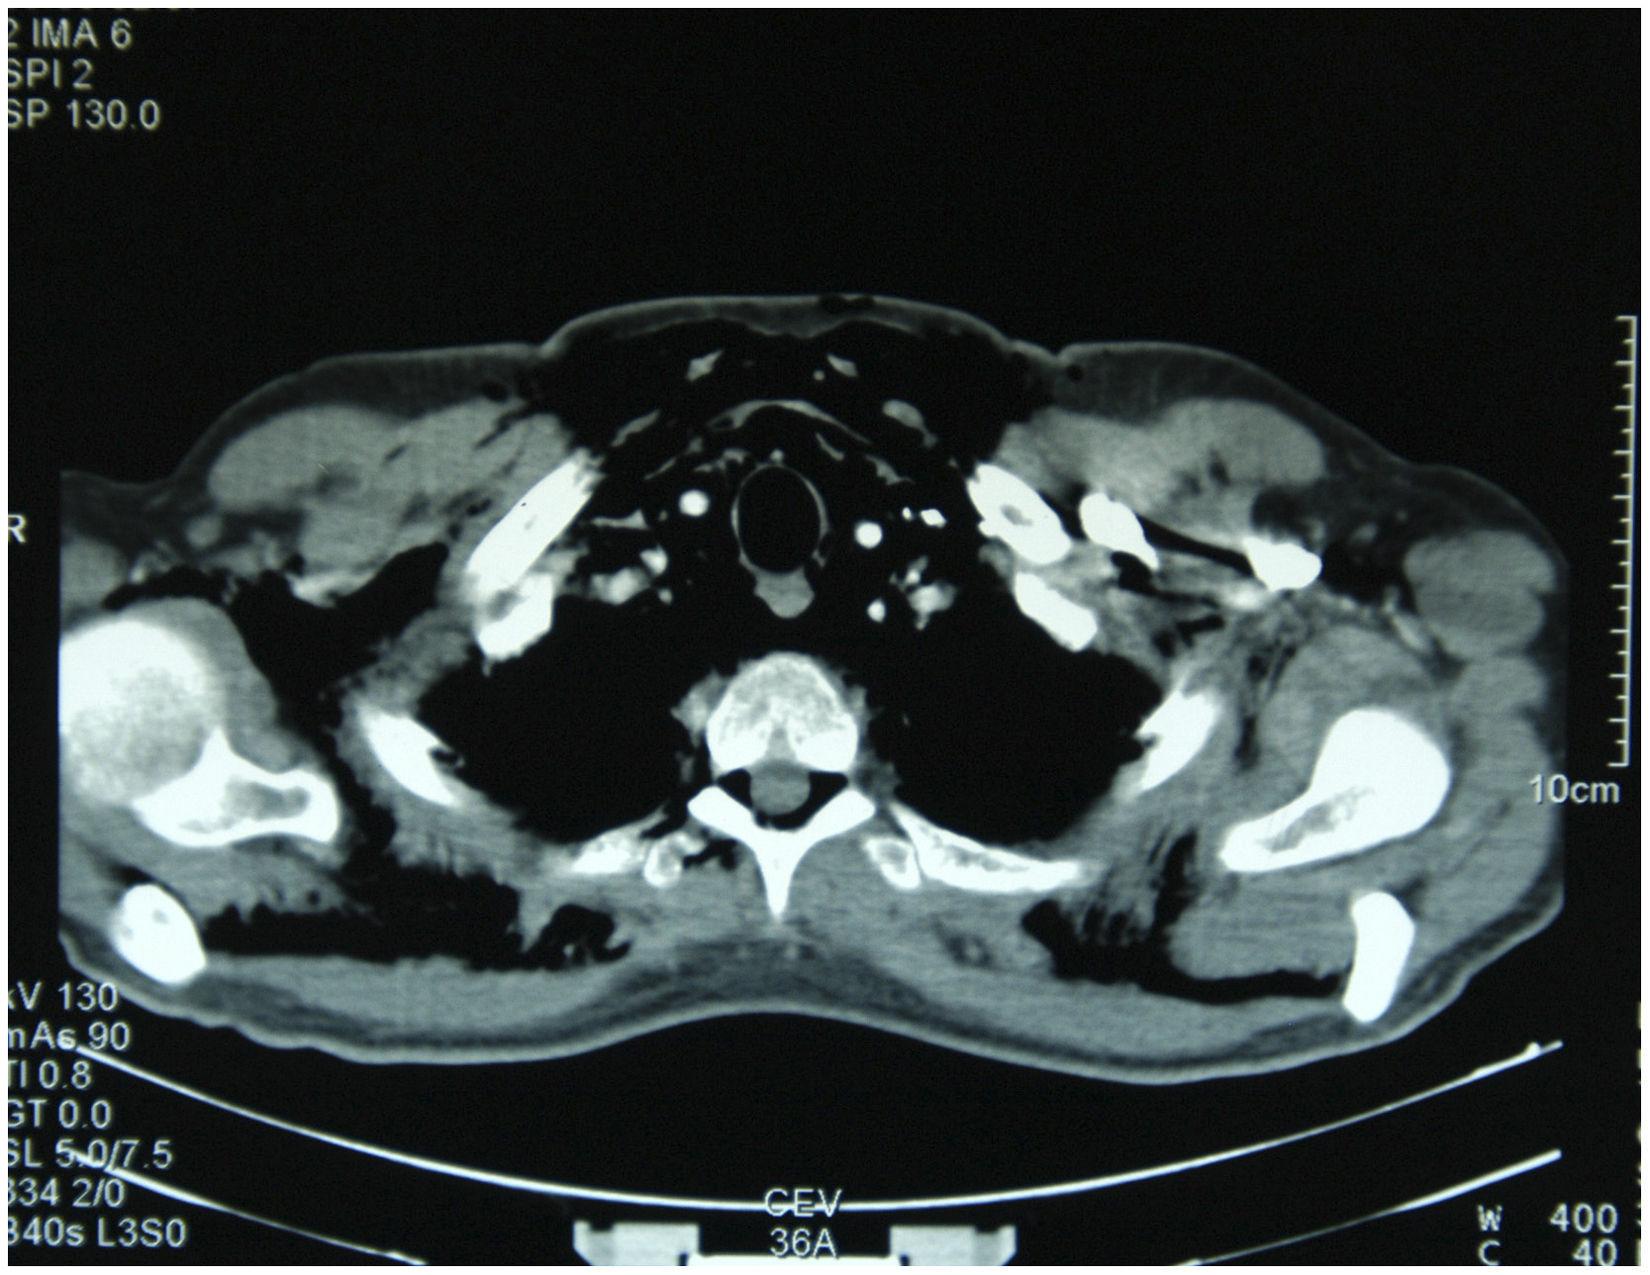

Download scientific diagram | Enfisema mediastínico. from publication: Traumatismos cervicales | Introduction and objectiveNeck injuries are of great clinical interest because they can induce El enfisema intersticial produce síntomas evidentes y causas subyacentes. Conozca las formas de aliviar los síntomas y hacer que la vida cotidiana sea más llevadera. Enfisema subcutáneo cervical y supraclavicular bilateral. En la pulsioximetría basal se mostraba una saturación de oxígeno del 97%, con frecuencia